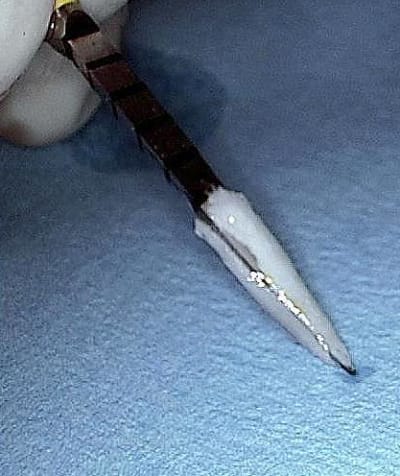

j'ajoute des photos pour le foret et la cavité osseuse dans quelques minutes.

07/07/2012 à 00h47

des photos d'un cas d'aujourd'hui avec le shuttle retiré ( 8 premières photos)

les 4 dernières c'est avec le foret , la dernière photo c'est un cas d'extraction implantation d'aujourd'hui aussi on voit la nouvelle alvéole après le forage ( désolé pour la qualité de photo...)